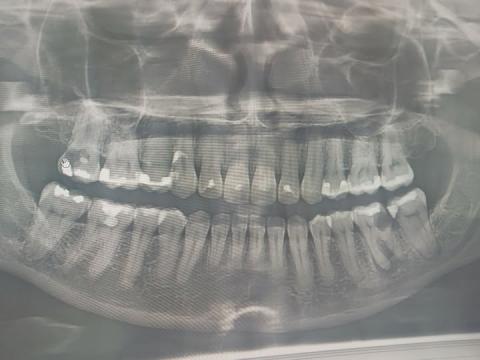

My name is Carlo, and this also happened to me. A dental friend advised me to remove my infected tooth. When I consulted other dentists, they also suggested extraction. The reason? They said my bone level was shallow and the infection inside the tooth was severe.

But I started to ask: Is removing the tooth always the best solution? Or is it simply the cheaper option?